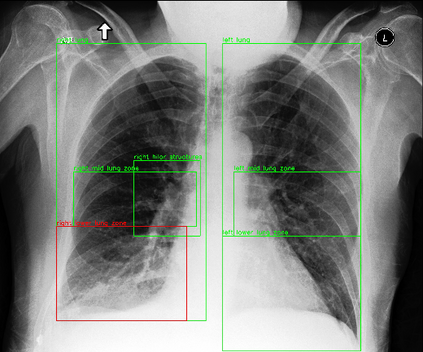

Despite the progress in utilizing deep learning to automate chest radiograph interpretation and disease diagnosis tasks, change between sequential Chest X-rays (CXRs) has received limited attention. Monitoring the progression of pathologies that are visualized through chest imaging poses several challenges in anatomical motion estimation and image registration, i.e., spatially aligning the two images and modeling temporal dynamics in change detection. In this work, we propose CheXRelNet, a neural model that can track longitudinal pathology change relations between two CXRs. CheXRelNet incorporates local and global visual features, utilizes inter-image and intra-image anatomical information, and learns dependencies between anatomical region attributes, to accurately predict disease change for a pair of CXRs. Experimental results on the Chest ImaGenome dataset show increased downstream performance compared to baselines. Code is available at https://github.com/PLAN-Lab/ChexRelNet

翻译:尽管在利用深层学习实现胸前射线解释和疾病诊断任务自动化方面取得了进展,但连续的胸前X射线(CXRs)之间的变化受到的注意有限。通过胸前成像可视化的病理进展监测在解剖运动估计和图像登记方面带来了若干挑战,即在空间上对两种图像进行匹配,在变化检测中模拟时间动态。在这项工作中,我们提议CheXRelNet,这是一个神经模型,可以跟踪两个CXRs之间的纵向病理变化关系。CheXRelNet包含当地和全球的视觉特征,利用图像间和图像内解剖学信息,并学习解剖区域属性之间的依赖性,准确预测两对CXR的疾病变化。Chest ImaGenome数据的实验结果显示,与基线相比,下游的性能有所增加。代码可在https://github.com/PLAN-Lab/CexRelNet上查阅。